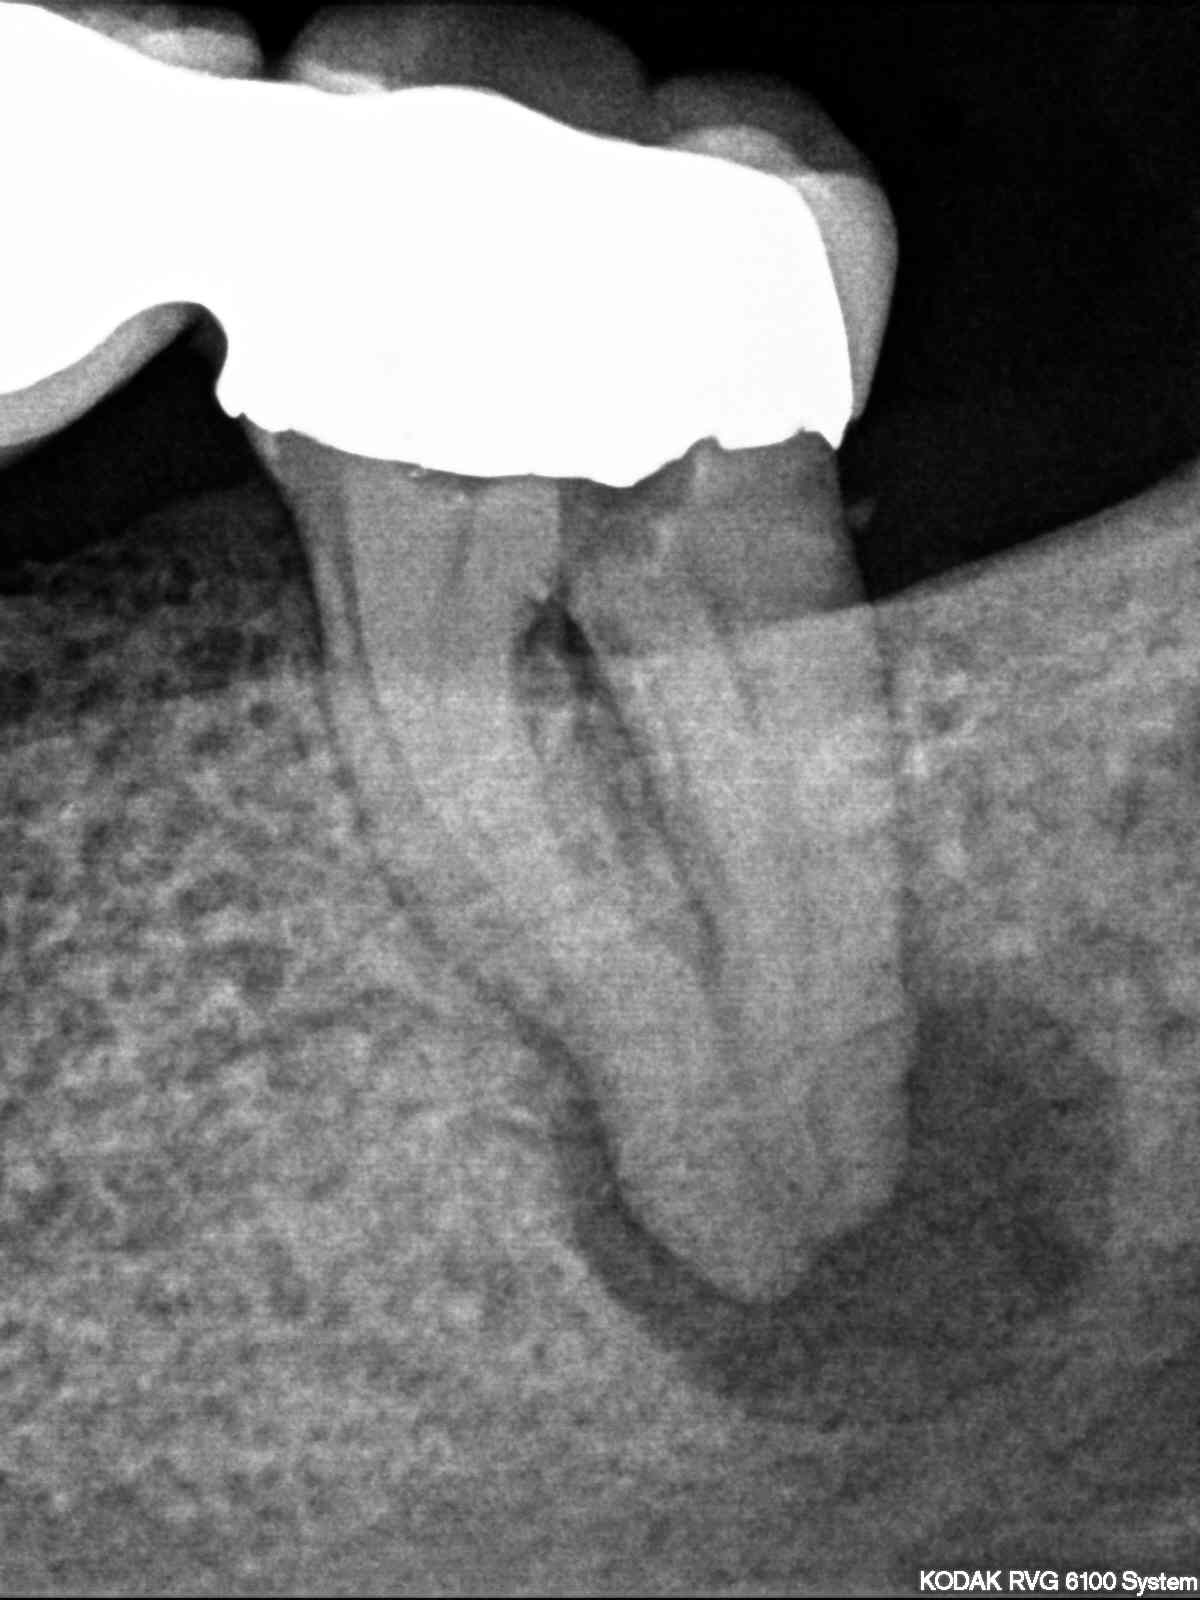

R2

1200 × 1600

Hyflex Fallbeispiel (2/3)